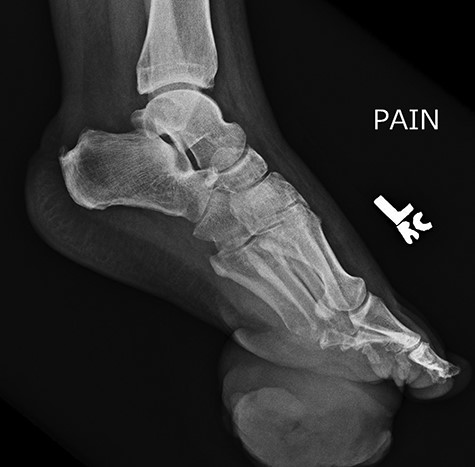

Repeat lateral X-ray views of the foot, 2 months later, showed ‘interval appearance of large soft tissue mass, plantar to the phalanges’. The differential diagnostic consideration by the imaging studies included ‘phlegmon, abscess, hematoma, or less likely a rapidly growing neoplasm’.

Approximately 2 months following surgical excision of the tumor, the patient presented with a significantly enlarged and painful recurrence of the mass (Fig. 5). Repeat X-rays of the foot showed ‘interval large soft tissue mass’ (Fig. 6). Nuclear three-phase bone scan was ‘suspicious for osteomyelitis or tumor involvement of bone’.